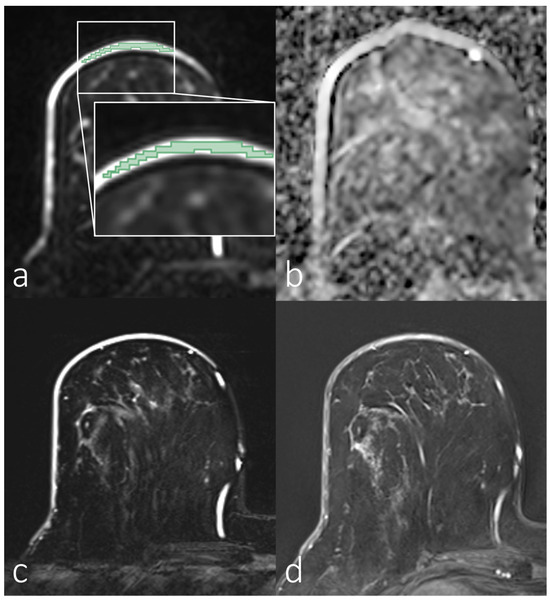

3.2. Analyses of First-Order Statistics Using the ADC

3.3. Evaluation of SNR in the Skin for Assessing ADCs in Skin Pathologies